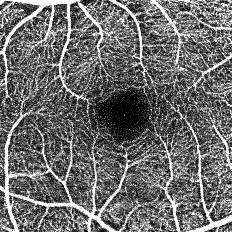

OCT Angiography の画像

■ 最短約3秒の短い検査時間で,目が動く被検者の血管画像も高精細に再現

毎秒約7万本の高速スキャンにより,最短約3秒の検査時間でOCT Angiographyの画像を取得できる。これにより,被検者の負担を軽くすることに加え,目が動くことによる画像への影響が軽減され,高精細な画像を得ることができる。また,わずか2クリックの簡単な操作で,自動で鮮明な画像を取得することが可能。